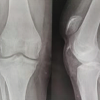

A 37-year-old male right hand dominant person presented with pain, swelling, and difficulty in performing hand movements of the right hand after punching a wall. The patient presented to us immediately on the day of injury. There was a diffuse swelling and tenderness over the ulnar aspect of the right hand. Active movements of the ring and little fingers were restricted and associated with severe pain. Radiographs taken at the time of presentation showed a dorsally displaced partial articular fracture of the fourth and fifth metacarpal base shown in (Fig. 1).